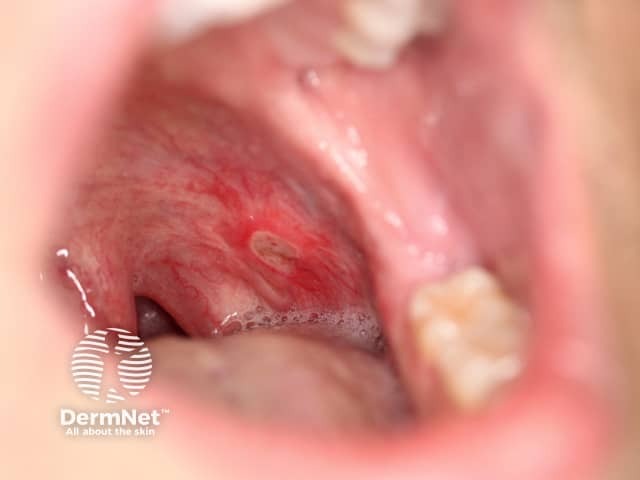

Oral involvement occurs in 8-9% of Crohn disease and may include:

Oral Crohn disease